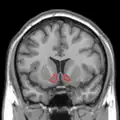

Nucleus accumbens

Approximate location of the nucleus accumbens in the brain